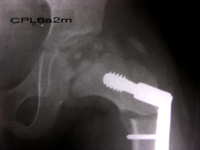

En otros tiempos la enfermedad  de Perthes era tratada colocándoles al paciente un aparato para no cargar peso (Aparato de Tadjan), se les indicaba reposo prolongado en cama o uso de muletas tratando de evitar peso sobre la cadera,  esta forma de pensamiento en la actualidad no es valida y el CONCEPTO ACTUAL ES EL DE CONTENCION DE LA CABEZA FEMORAL DENTRO DEL ACETABULO,  esto se logra con colocación de yesos, férulas o cirugía. Los dos primeros se usan por un promedio de 18 a 24 meses. La cirugía consiste en una osteotomía del fémur (corte del fémur en la base del cuello) para redirigir la cabeza femoral al acetábulo.